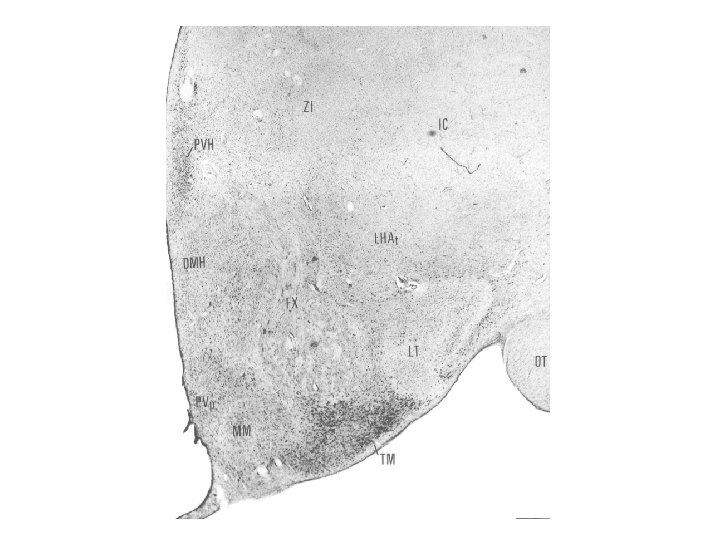

Nucleus dorsomedialis hypothalami A hypothalamus középső részében, a harmadik agykamra két oldalán, a nucleus ventromedialis felett helyezkedik el. Neuronjai több szubdivíziót alkotnak, melyek a táplálékfelvétel központi szabályozásában és a stressz válaszban visznek szerepet.

VENTROMEDIAL NUCLEUS - lesioning of this nucleus (electrolytic or gold thioglucose) induces hyperphagia and resulted in extreme obesity - stimulation of ventromedial neurons suppress feeding - injections of leptin and urocortin into the nucleus inhibit, injections of NPY, β-endorphin or galanin stimulate feeding - local administration of 2 -deoxy-glucose (cellular glucoprivation) evokes rapid increases in plasma levels of glucose

UROCORTINS - urocortin III. neurons are located in the dorsomedial hypothalamus with ventromedial projections - urocortin III. neurons here co-express enkephalin - neurons here contain leptin receptors (Ob-Rb receptors) - neurons here activated by leptin (c-fos expression) - urocortin III. acts on CRH 2 receptors in the ventromedial nucleus - urocortin acts as endogenous activators of anorexia. Its anorexic effect appears to be more potent than that of CRH